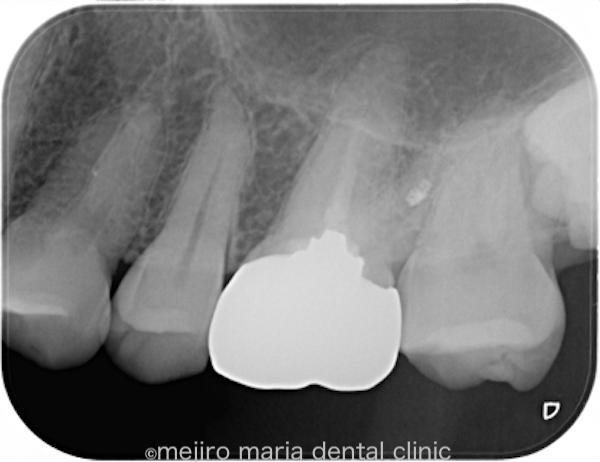

治療後の様子

今後は通常と同じように2年間の経過観察を行い、治療の経過を確認していく予定です。